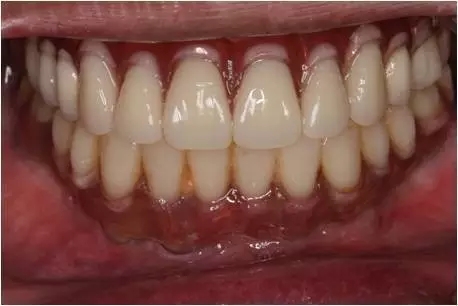

患者男性,51歲,全口無(wú)牙,下頜骨量尚可,上頜后牙區(qū)上頜竇底剩余骨高度嚴(yán)重不足,前牙區(qū)牙槽突較豐滿,主訴希望全口種植固定義齒修復(fù)。于2015年 9月接受種植治療:上頜采用All-on-4種植方案、下頜采用常規(guī)種植6顆種植體方案,種植后行即刻修復(fù)(圖1-2)。